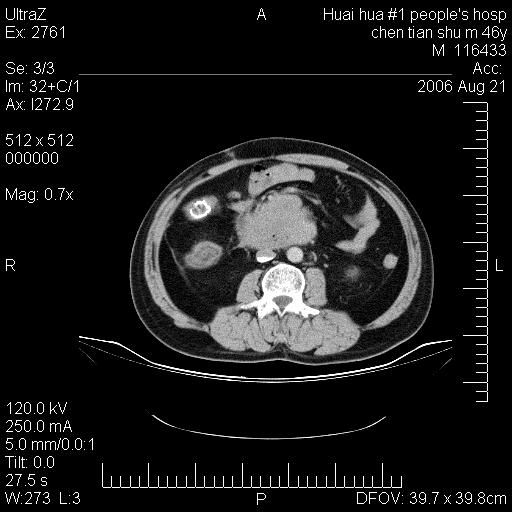

患者,男,46y。腹痛2月,消瘦。

十二指肠水平段占位,考虑间质瘤或平滑肌瘤。

肿块较大,腹膜后占位,境界欠清,周边脂肪密度较高呈条状影,有没有脂肪肉瘤可能,

缺少完整的三期图像。考虑肠系膜脂膜炎mp(肿块型)。

鉴别:间质瘤(这么大而无囊变不可思议)、平滑肌瘤/肉瘤、淋巴瘤、类癌,脂肪类肿瘤、转移瘤等。

十二指肠水平段占位,考虑间质瘤。

首先考虑小肠间质瘤。

十二指肠水平段软组织密度占位,考虑间质瘤可能性大。

腹膜后占位,境界欠清,考虑来源于十二指肠病变,间质瘤或平滑肌肉瘤可能性大。建议活检。

手术病理结果:原发性小肠恶性淋巴瘤(primary gastrointestinal lymphoma,pgil)是原发于胃肠的淋巴网织系统的恶性肿瘤,在结外淋巴瘤中居第一位,该病少见,临床无特异性,诊断困难,术前主要依靠影像学诊断。胃肠道本身具有较丰富的淋巴组织,因而胃肠原发性淋巴瘤是结外淋巴瘤最常见的部位,文献报道约占胃肠道恶性肿瘤的1%~4%,其中胃约占50%~70%,小肠约占35%~70%,结肠约占4%~6%。影像检查在pgil的诊断及分期中有重要的作用,ct是很有价值的检查方法。

胃肠淋巴瘤病理特点:胃肠道原发性淋巴瘤起源于胃肠壁固有层和黏膜下层的淋巴组织即胃肠粘膜相关淋巴组织(malt),多为粘膜相关淋巴瘤。病理上通常为非霍奇金淋巴瘤,且决大多数来源于b淋巴细胞,很少见于霍奇金淋巴瘤。胃肠原发淋巴瘤比胃肠道癌的发病率要低的多,最常见于胃,其病因可能跟幽门螺杆菌感染有关。幽门螺杆菌能引起胃粘膜损害,引起炎性及免疫反应,淋巴细胞聚集并形成滤泡,可影响胃的正常生理功能,导致胃淋巴瘤的发生。单纯性小肠淋巴瘤是常见好发于回盲末端,受累的肠段较长,可单发、多发,甚至累及整个小肠。原发性大肠淋巴瘤罕见,以直肠和盲肠最多见。病变大体观可表现为胃肠腔内外的肿块,也可表现为从黏膜下到浆膜面肠壁的纵向浸润,并且常常伴有肠系膜淋巴结肿大。任何情况下,肿瘤几乎总是导致一定程度的肠壁增厚,可对称或不对称,病变与正常组织间常无明确分界,肠腔可狭窄、正常或动脉瘤样扩张,后者主要是肿瘤在肠壁内浸润,破坏肠壁内植物神经丛所致。以上改变成为ct检测病变的病理基础。

肠道淋巴瘤的ct表现分为4类

1) 壁内浸润型, (2)多发结节型, (3)肠系膜受累伴腔外肿块型(本型就是),(4)肿块型。